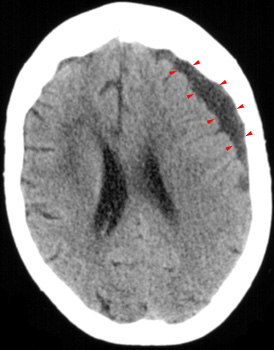

Head CT > Trauma > Chronic Subdural Hematoma

Chronic Subdural Hematoma

Chronic

SDH becomes low density as the hemorrhage is further reabsorbed. It is

usually uniformly low density but may be loculated. Rebleeding often occurs

and causes mixed density and fluid levels.